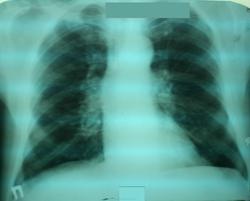

Мужичек, 71 год. Готовится к офтальмологической операции. Никаких жалоб и клиники, кроме плохого зрения. Приехал из глубинки. Говорит, что в больнице первый раз. Рентгенобследования никогда никакие не проходил. Доминантный вариант диагноза у коллег - саркоидоз. Первая мысль такая же. Но теперь под сомнениями. До фтизиатров пока не дошел. Ваши мнения, коллеги.

По снимкам ничего не скажу-гадание на кофейной гуще. Необходимы кт и морфологическая верификация.

Какие узлы? Где? Сосуды!

Сосуды тоже есть. Но чисто для сосудов замного)

Легочная гипертензия?

Обрубленность корней при перераспределении кровотока. С уважением, Д

Уважаемый коллега, фразы типа: " обрубленность", на практике каждый подбирает под себя. Те ребята, "на чьих плечах мы стоим " имели в виду отсутствие сосудистых теней дальше корня, в прикорневой и плащевой. В данном случае какие - то тени сосудов видны дальше корня.( скорее вены)

Уважаемый коллега! Я имел ввиду симптом "прыжка калибра", как проявление легочной артериальной гипертензии (стр.57 книги К.Б.Тихонова Рентгенологическая симптоматика сердечной недостаточности 1985 год). Возможно я не прав, поэтому поставил знак вопроса. Мужчине - 71 год, так что предположение о наличии признаков сердечной недостаточности вероятно.

не знаю как кто назвает, но изменение калибра сосудов не границе корней есть. Поэтому, как мне кажется, надо исключить сердечную патологию.

Синдром изменения корней легких включает любые отклонения от нормальной картины легких. Компьютерная томография с внутривенным контрастированием в настоящее время является ведущим методом диагностики патологических изменений корня легкого.